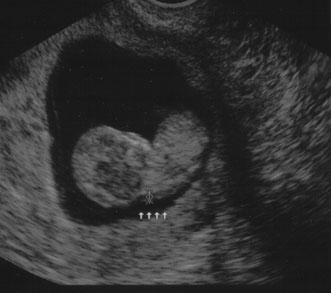

Nuchal edema is an echo-free space between the skin line and the soft tissue overlying the cervical spine. Nuchal edema is caused by subcutaneous accumulation of fluid and has diverse etiology, including aneuploidies, cardiovascular and pulmonary defects, skeletal dysplasias, congenital infections, and hematologic and metabolic disorders. A nuchal translucency (NT) is obtained between 10 and 13 weeks' 6 days' gestational age (Fig. 8).31 A study at King's College Hospital in London found an NT of 3 mm was associated with a 4-times increase in the maternal age related risk for aneuploidy. An NT greater than 4 mm resulted in a 29 times increased risk for trisomies 21, 18, and 13. Additionally, with a 4 mm or more NT, there was a high incidence of other anomalies and poor prognosis, whereas with just 3 mm and a normal karyotype, the outcome was usually normal. Table 8 lists the disorders associated with an increased nuchal translucency thickness.

Fig. 8. Normal nuchal translucency of 0.19 cm at 11 weeks' gestation.